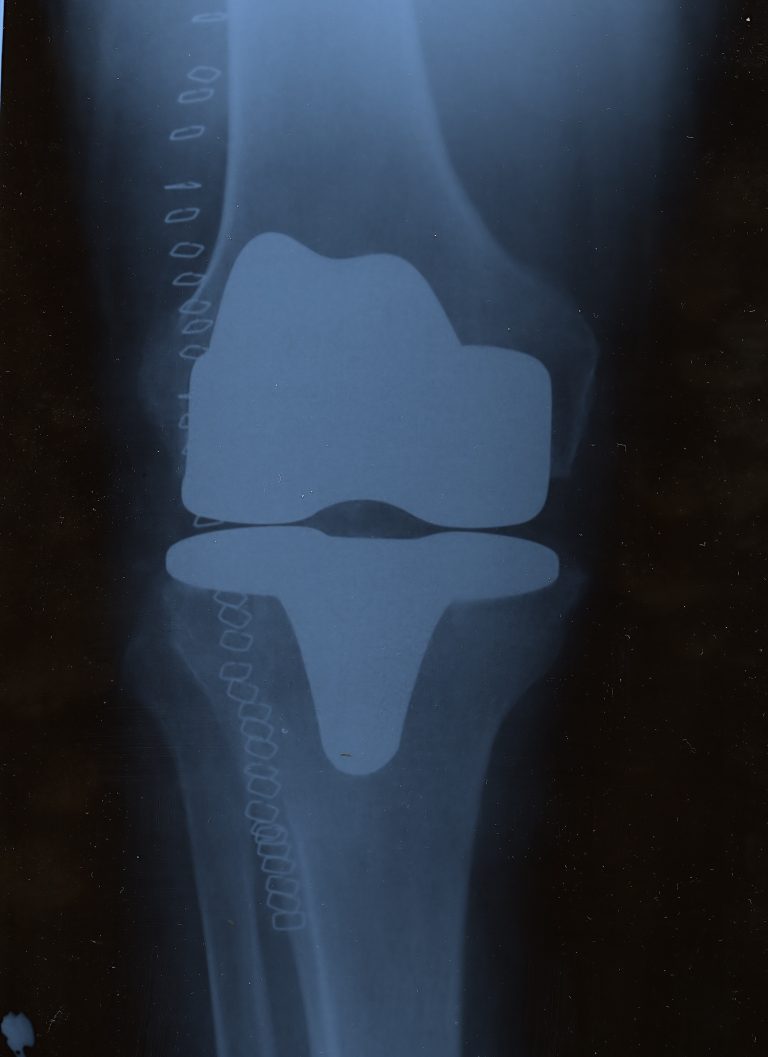

Ein künstliches Kniegelenk, auch Knieprothese bzw. umgangssprachlich „Künstliches Knie“ genannt, ist ein Ersatz für ein natürliches Kniegelenk. Insbesondere ersetzt es die abgenützten knorpeligen Gleit- und Oberflächen des Knies. Es kann aus Metall, Kunststoff oder Keramik hergestellt sein und wird im Rahmen einer Operation eingesetzt. Dabei werden die beschädigten, krankhaften Teile im Kniegelenk während des Eingriffs entfernt und durch das künstliche Implantat ersetzt. Je nach Ausmaß der Arthrose wird entweder das ganze Kniegelenk ersetzt (Knie-Totalendoprothese), oder nur ein Teil des betroffenen Gelenkabschnittes erneuert.

Deutliche Indikatoren für die Notwendigkeit einer Knieprothese sind das Auftreten von Nacht- und Ruheschmerzen, deutliche reduzierte Mobilität im Kniegelenk, sowie alle damit verbundenen Beschwerden, die eine schmerzfreie Bewältigung des Alltags beeinträchtigen können. Mittels Röntgen und MRT wird festgestellt, welche Teile des Knies erneuert werden müssen, und ob eine Knieendoprothese notwendig ist. Ein solches klinisches Bild zeigt, zu welchem Grad die Knorpel beschädigt sind und ob eine Knieprothese notwendig ist. Die medizinischen Bilder von Röntgen und MRT helfen dem behandelnden Orthopäden bzw. Kniespezialisten eine Diagnose zu stellen und liefern die nötigen Informationen, um über das weitere Vorgehen und die Wahl der richtigen Knieprothese zu entscheiden.

Das künstliche Kniegelenk wird während einer Operation eingesetzt. Je nach Ausmaß der Schädigung des Kniegelenks kann ein Teil des Knies ersetzt werden oder es erforderlich sein, dieses vollständig zu ersetzen. Diese Entscheidung trifft der behandelnde Arzt auf der Grundlage von Röntgen- und MRT-Aufnahmen vor der Operation.

Der letzte Ausweg für ein kaputtes Knie ist die Knietotalendoprothese – das künstliche Knie. Hierbei werden große Teile des Gelenks sowohl beim Unter- als auch beim Oberschenkel abgenommen und ein komplett neues Gelenk eingesetzt. In der Medizin ist der künstliche Kniegelenkersatz ein sehr erfolgreiches chirurgisches Verfahrenund mittlerweile weit verbreitet, um die Lebensqualität der/des Betroffenen drastisch zu verändern. Der Gelenkersatz wird dabei aus Metall und Kunststoff hergestellt. Die Ober- und Unterschenkel-Komponenten bestehen hierbei aus Metall, wobei die dazwischenliegende Gleitfläche aus Polyethylen hergestellt wird. Die Knieprothese kann zusätzlich auch die Kniescheibe ersetzen.